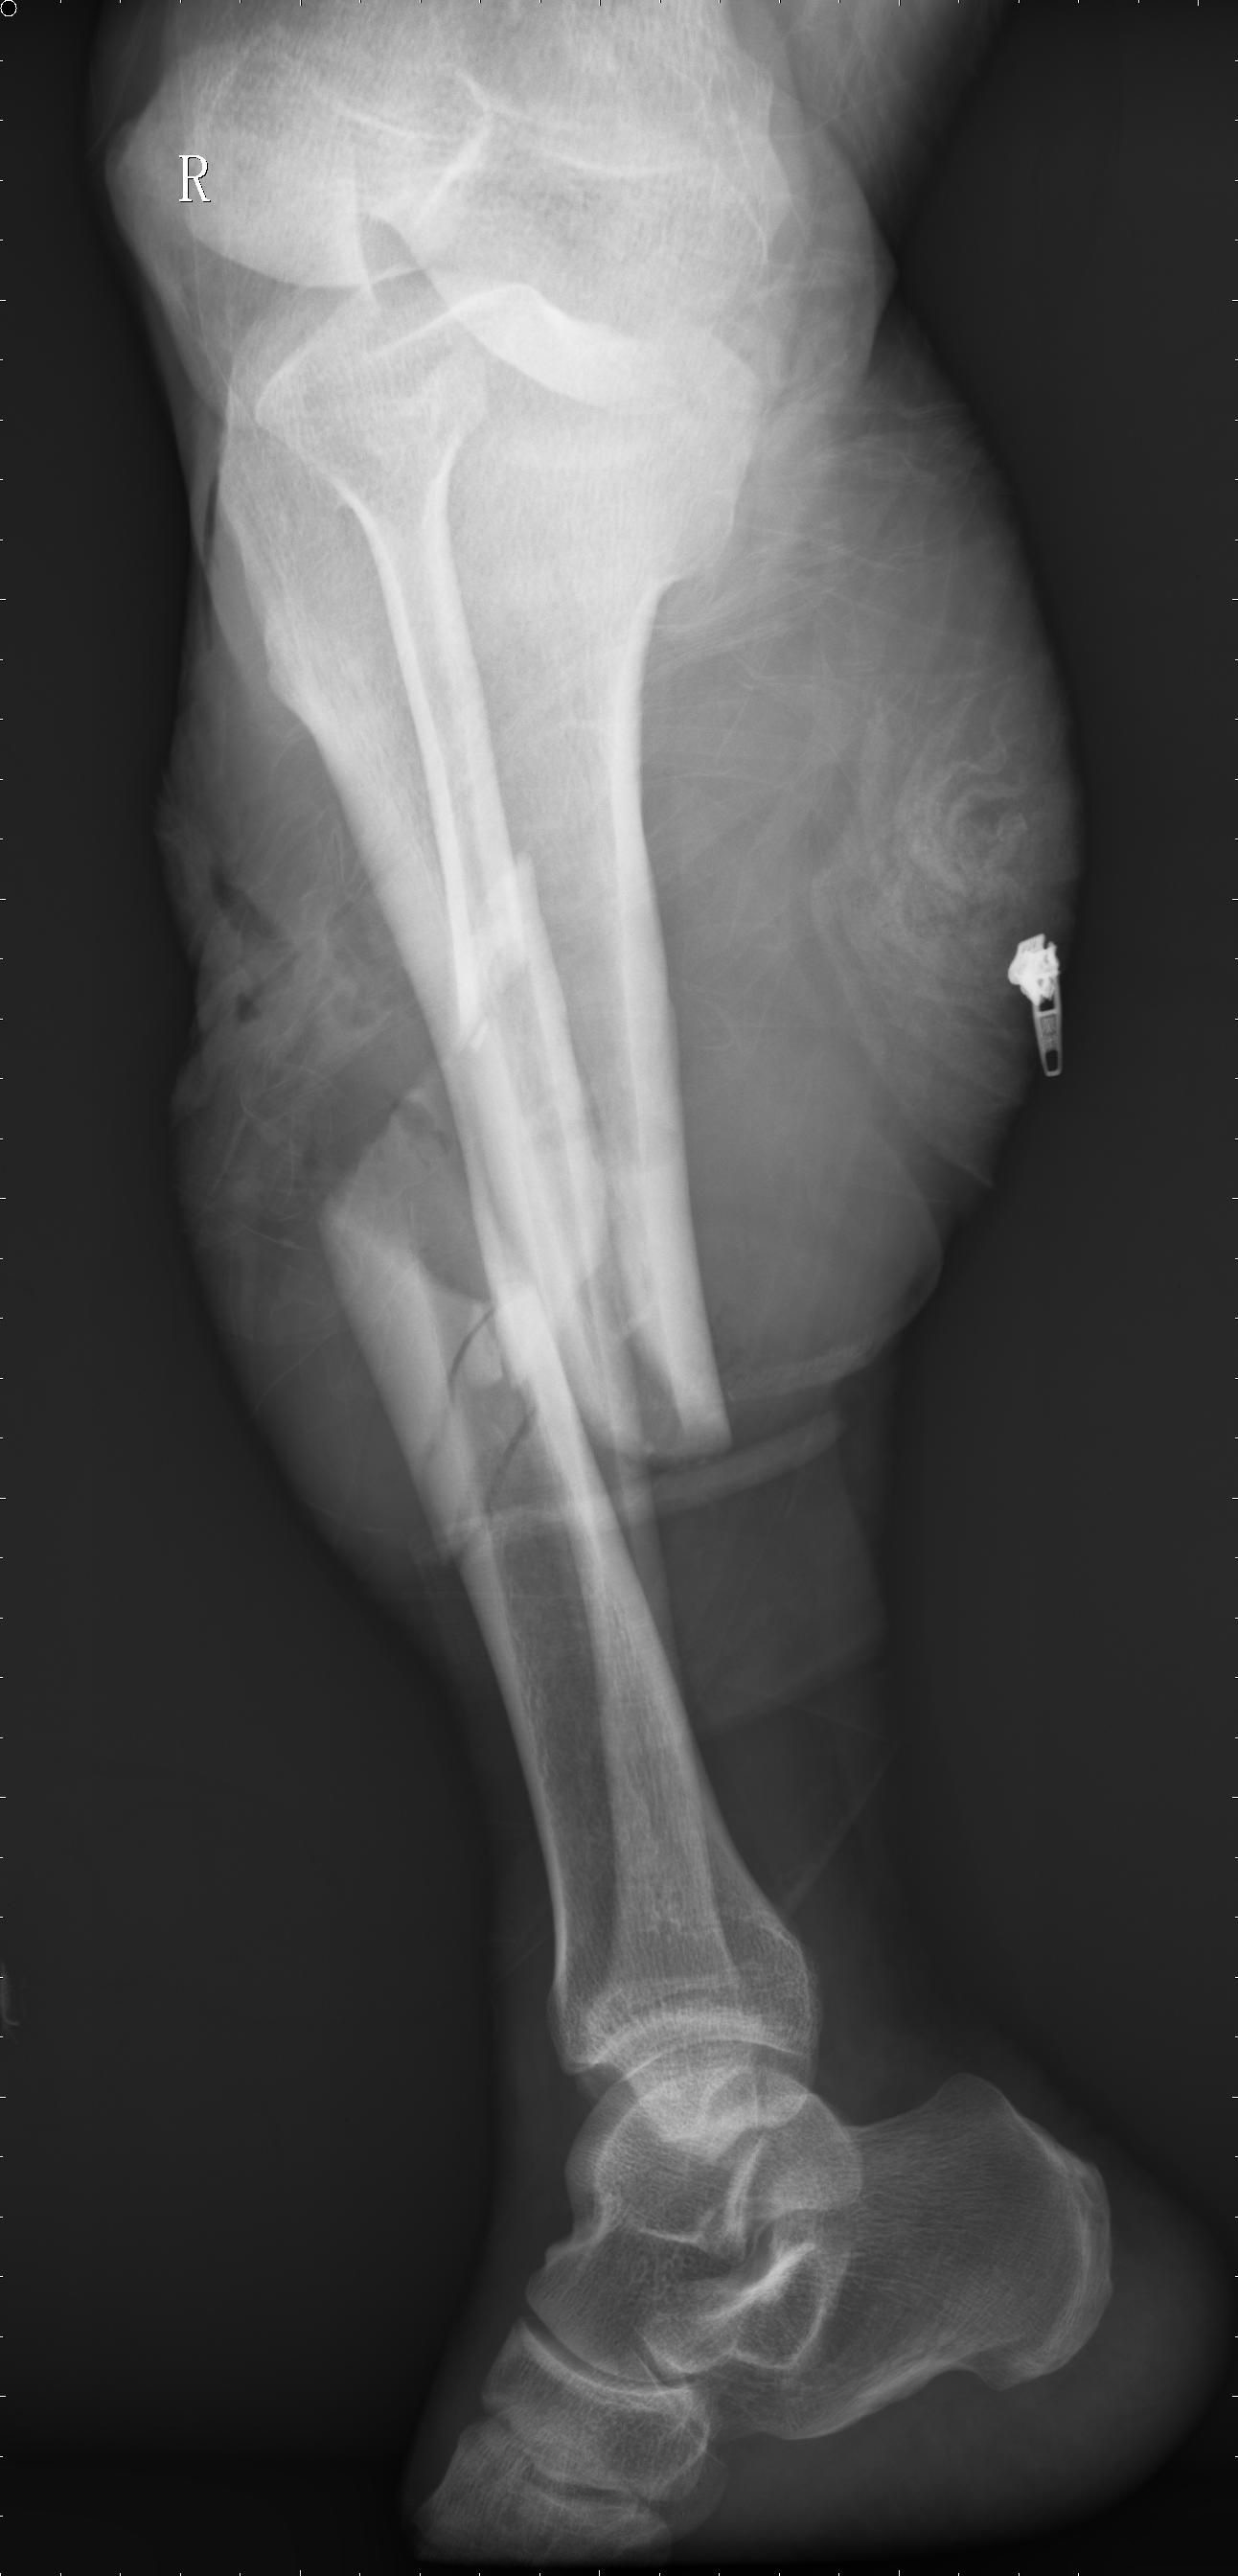

開放性骨折的定義及應(yīng)急處理

凡骨折時(shí),合并有覆蓋骨折部位的皮膚及皮下軟組織損傷破裂,使骨折斷端和外界相通者,稱為開放性骨折。開放性骨折是創(chuàng)傷骨科的常見病、多發(fā)病,隨著社會(huì)的發(fā)展,現(xiàn)代化高速工具的使用,所造成的開放性骨折日趨嚴(yán)重,病情越發(fā)復(fù)雜、治療更加困難。

開放性骨折癥狀

局部表現(xiàn)

肱骨髁上骨折

1、骨折的一般表現(xiàn) 為局部疼痛、腫脹和功能障礙。骨折時(shí),骨髓、骨膜及周圍組織血管破裂出血,在骨折處形成血腫,以及軟組織損傷所致水腫,使患肢嚴(yán)重腫脹,甚至出現(xiàn)張力性水皰和皮下瘀斑,由于血紅蛋白的分解,可呈紫色、青色或黃色。

骨折局部出現(xiàn)劇烈疼痛,特別是移動(dòng)患肢時(shí)加劇。局部腫脹和疼痛使患肢活動(dòng)受限,如為完全性骨折,可使受傷肢體活動(dòng)功能完全喪失。

2、骨折的特有體征

(1)畸形:骨折段移位可使患肢外形發(fā)生改變,主要表現(xiàn)為短縮、成角或旋轉(zhuǎn)。

(2)異?;顒?dòng):正常情況下肢體不能活動(dòng)的部位,骨折后出現(xiàn)不正常的活動(dòng)。

(3)骨擦音或骨擦感:骨折后,兩骨折端相互摩擦?xí)r,可產(chǎn)生骨擯音或骨擦感。